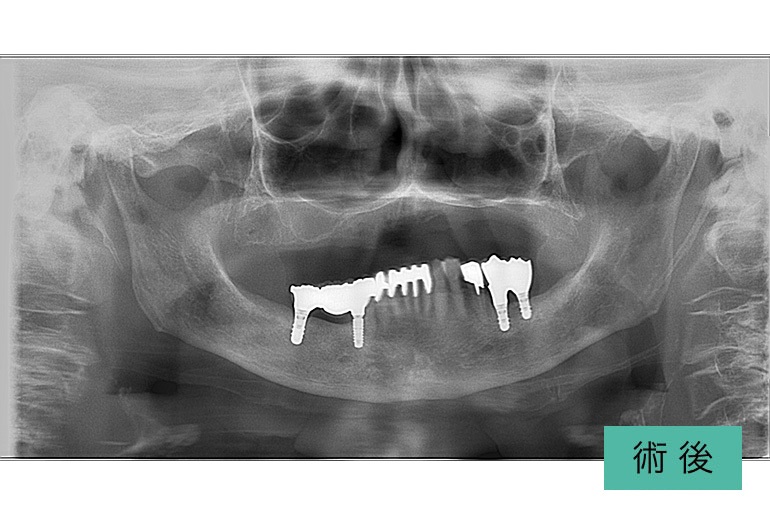

インプラント④

| 治療内容 | 入れ歯が合わなくてずっと噛みにくい。 下顎の入れ歯は不安定になるので、下顎の歯が無いところはインプラント治療をする。 上顎の入れ歯は患者さんが許容されてますので、保険治療の入れ歯で治療をする。 下顎を安定して治療すれば、上顎の入れ歯はどの歯科医師が作成しても噛める入れ歯を作ることは簡単。 将来、当院まで来院できなくなったとしても、どんな先生が治療しても上手くいくはずなので心配がない。 治療後、9年経過してますが上顎の入れ歯を作成するのみで対応できています。 |

|---|---|

| 治療期間・回数 | 半年、30回 |

| 費用(税込) | インプラント+セラミック冠 ¥2,596,000 ※自由診療 上顎入れ歯 ※保険診療 |

| リスク・副作用 | 出血、痛み、外科的治療、下歯槽神経麻痺 |